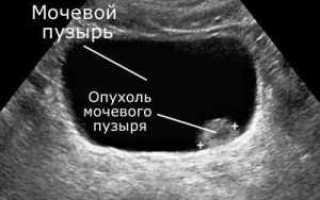

- Ультразвуковое исследование. Звуковые волны способны уточнить размер, тип и структуру образования. Также выясняется, не задеты ли соседние органы;